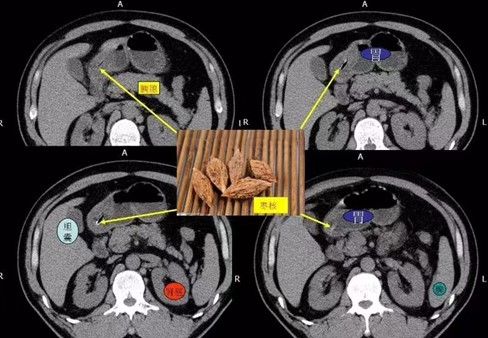

非金属异物或透光异物应建议进行CT检查(如鱼刺、枣核、鸡骨头等),可直观了解有无异物,异物的位置、大小、形态及毗邻关系,并可通过后处理技术进一步了解异物具体情况,还可进一步评估异物周围组织损伤的程度。如异物滞留体内时间较长,尤其食管异物,在行异物取出术前应行CT检查,当怀疑异物合并腹膜炎、脓肿、瘘管、食管异物穿孔等需要外科手术干预时,可行CT检查。需要注意的是,即便完善胸腹部CT检查,可能由于胃肠内容物等原因,少部分的消化道异物仍无法明确诊断。

食管颈段异物(枣核)

异物(枣核)自行掉入胃腔内